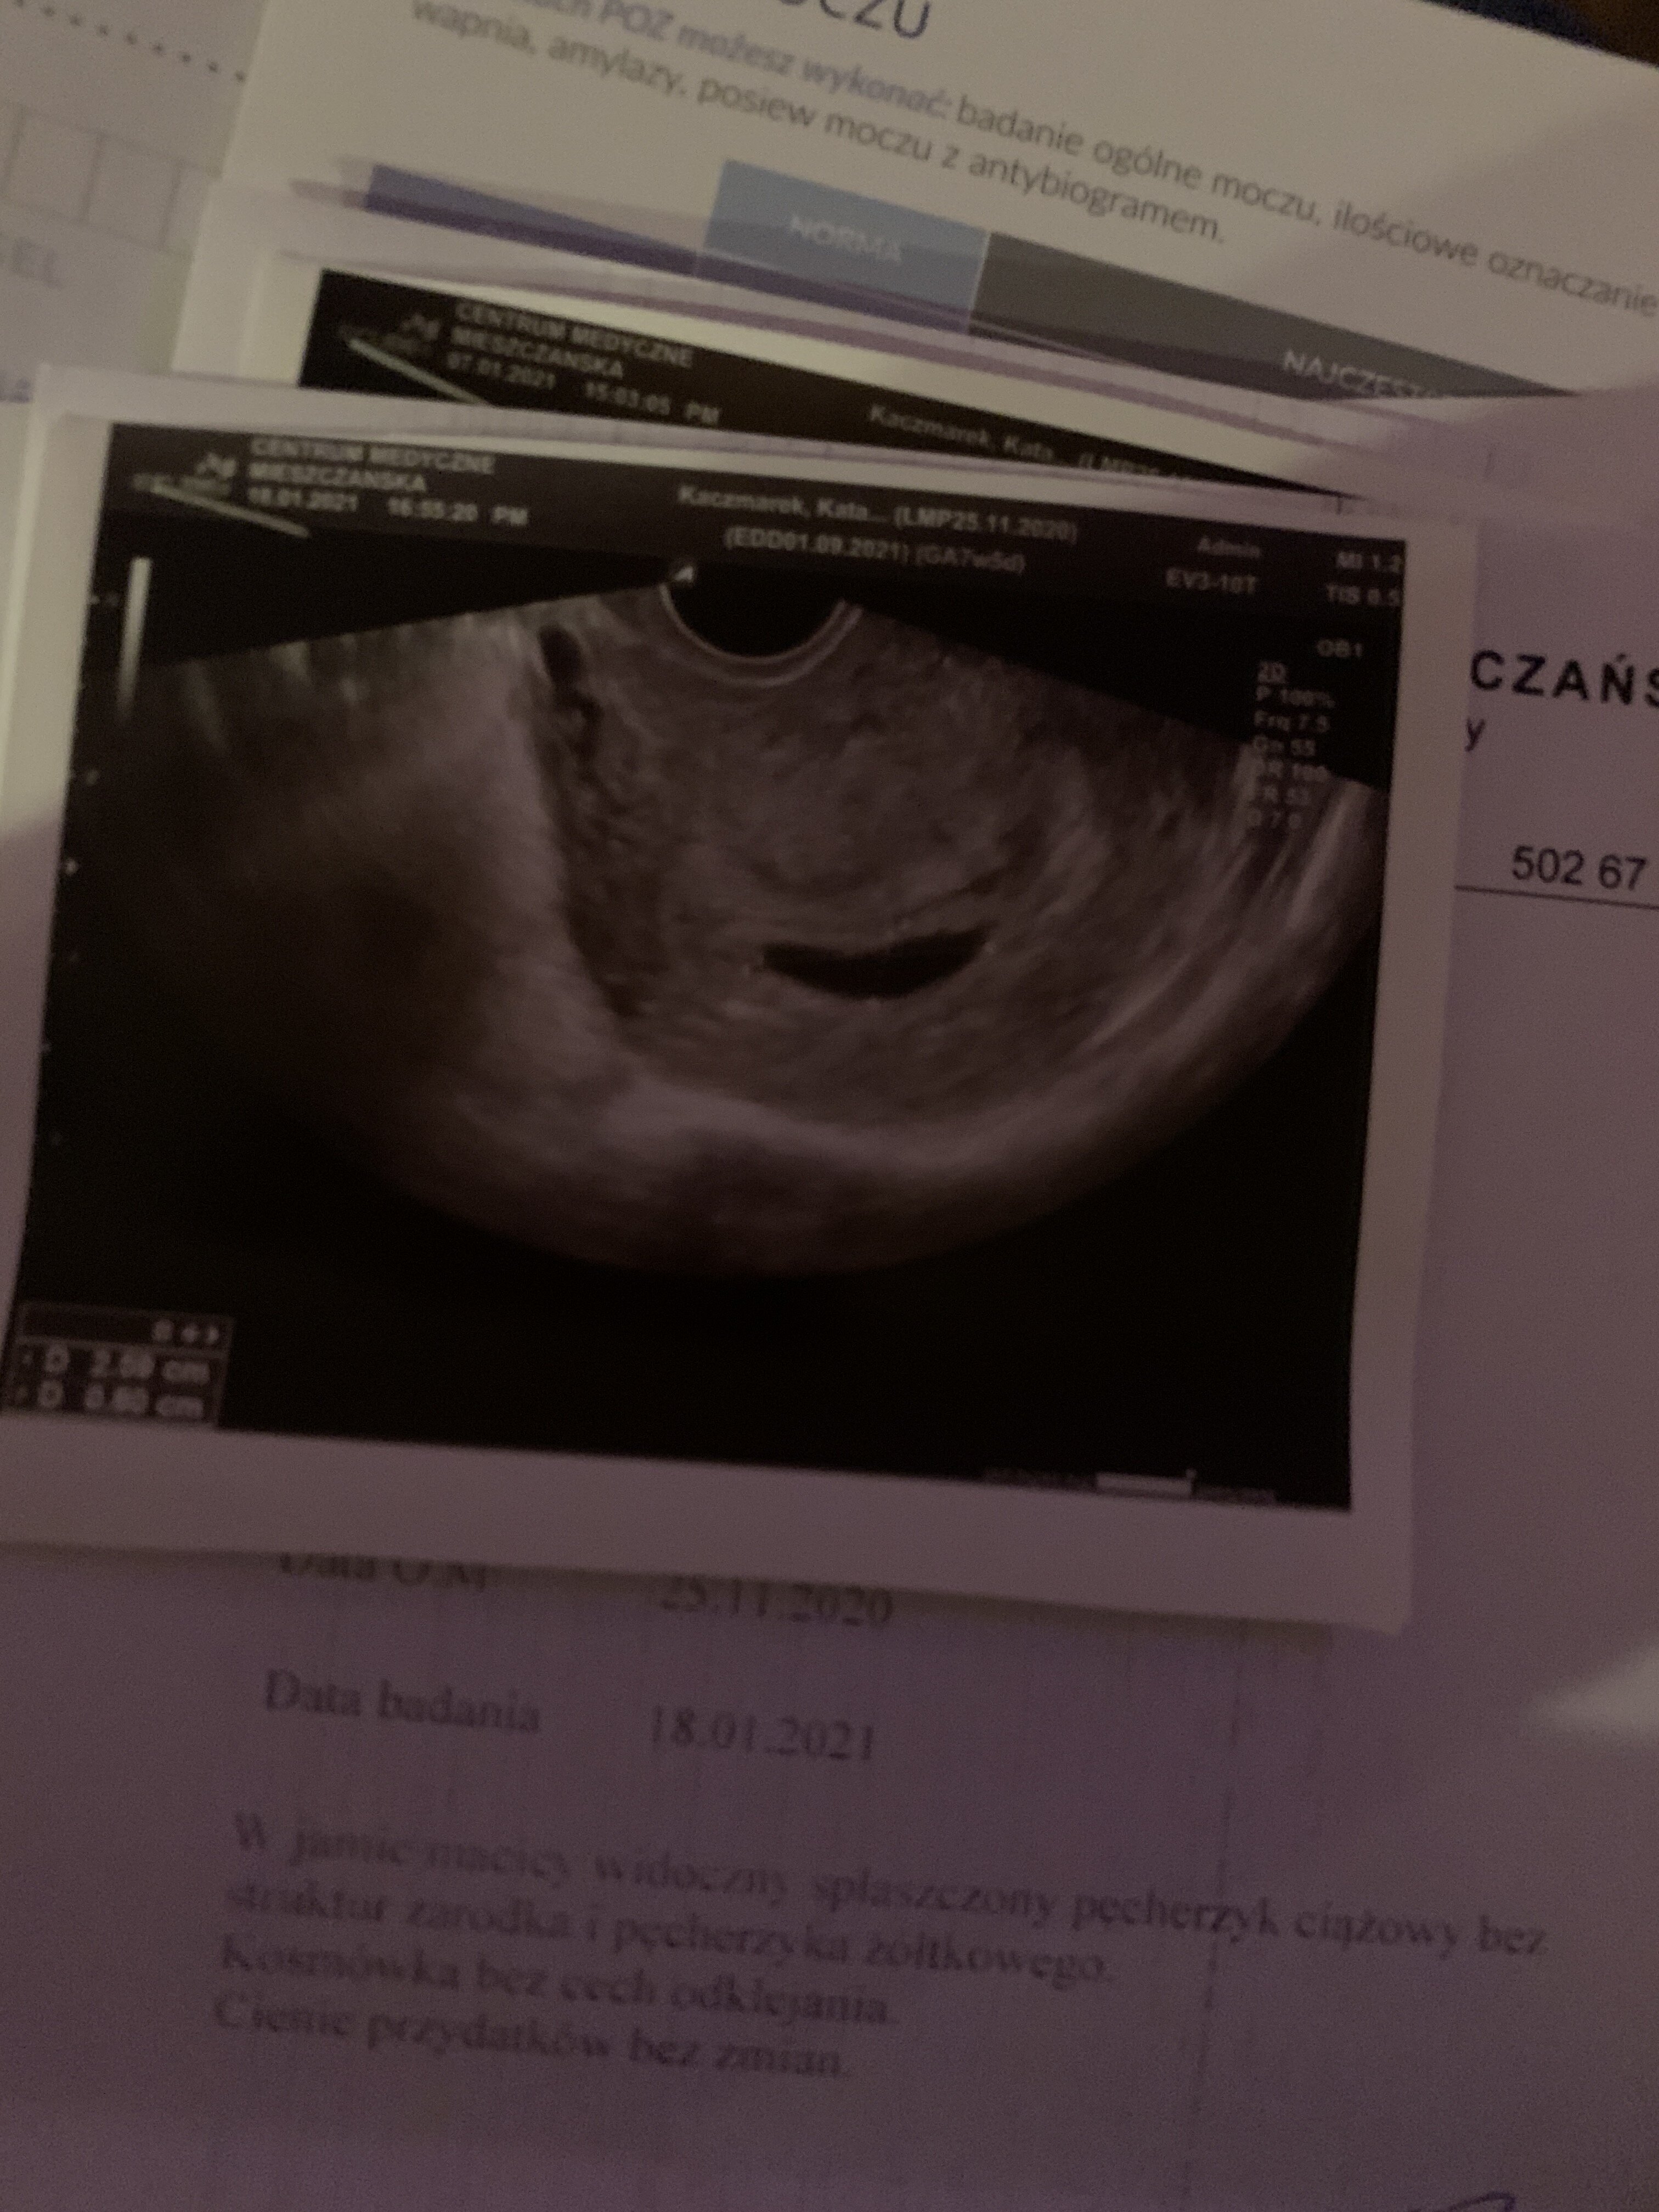

Puste jajo

Wczoraj byłam na wizycie już kolejnej po 10 dniach ... i niestety diagnoza potwierdzona puste jajo płodowe . Nie wiem czemu od początku tej „ciazy” byłam bardzo zestresowana ... czułam ze coś jest nie tak . Starałam się odganiać złe myśli , ale było ciężko . W pierwszej ciąży dwa lata temu wszystko przebiegało idealnie i bez problemowo ... tym bardziej nie mogę zrozumieć co się stało i w czym był problem . W piątek mam dostać tabletkę na wywołanie porodu , sama nie wiem ile to wszystko będzie trawało i na co mam się przygotować ... lekarz za wiele nie powiedział , poza tym żeby się nie przejmować ... chcielibyśmy starać się ponownie o maluszka , nie wiemy za bardzo po jakim czasie jest to możliwe . Czy któraś z was miała może taką sytuacje i jest w stanie się wypowiedzieć ?

• 8CBFB378-96F5-4405-A9CD-8F10A2BF62FA.jpeg

8CBFB378-96F5-4405-A9CD-8F10A2BF62FA.jpeg

1,4 MB · Wyświetleń: 394